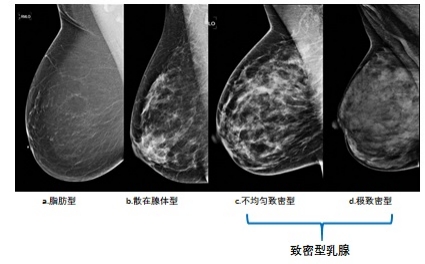

但乳腺X线检查对结节的检出却要受乳房腺体致密程度的影响,如果乳房内腺体少、脂肪多,那结节就容易显示;但如果腺体多、脂肪少,结节就不容易显示,甚至造成漏诊。而此时超声检查就可以弥补X线检查在致密型腺体中容易漏诊的不足。

所以乳腺癌的诊治指南都会建议对于乳腺X线检查提示致密型乳腺的女性人群,需要乳腺X线检查联合超声检查来提高乳腺癌筛查的敏感度。而乳腺磁共振检查可作为乳腺X线检查、乳腺临床体检或乳腺超声检查发现的疑似病例的补充及进一步检查,以及参与乳腺癌高危人群的筛查。